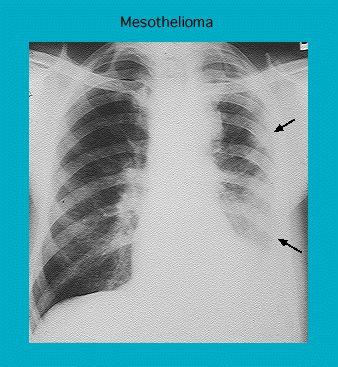

Radiograph of a pleural mesothelioma